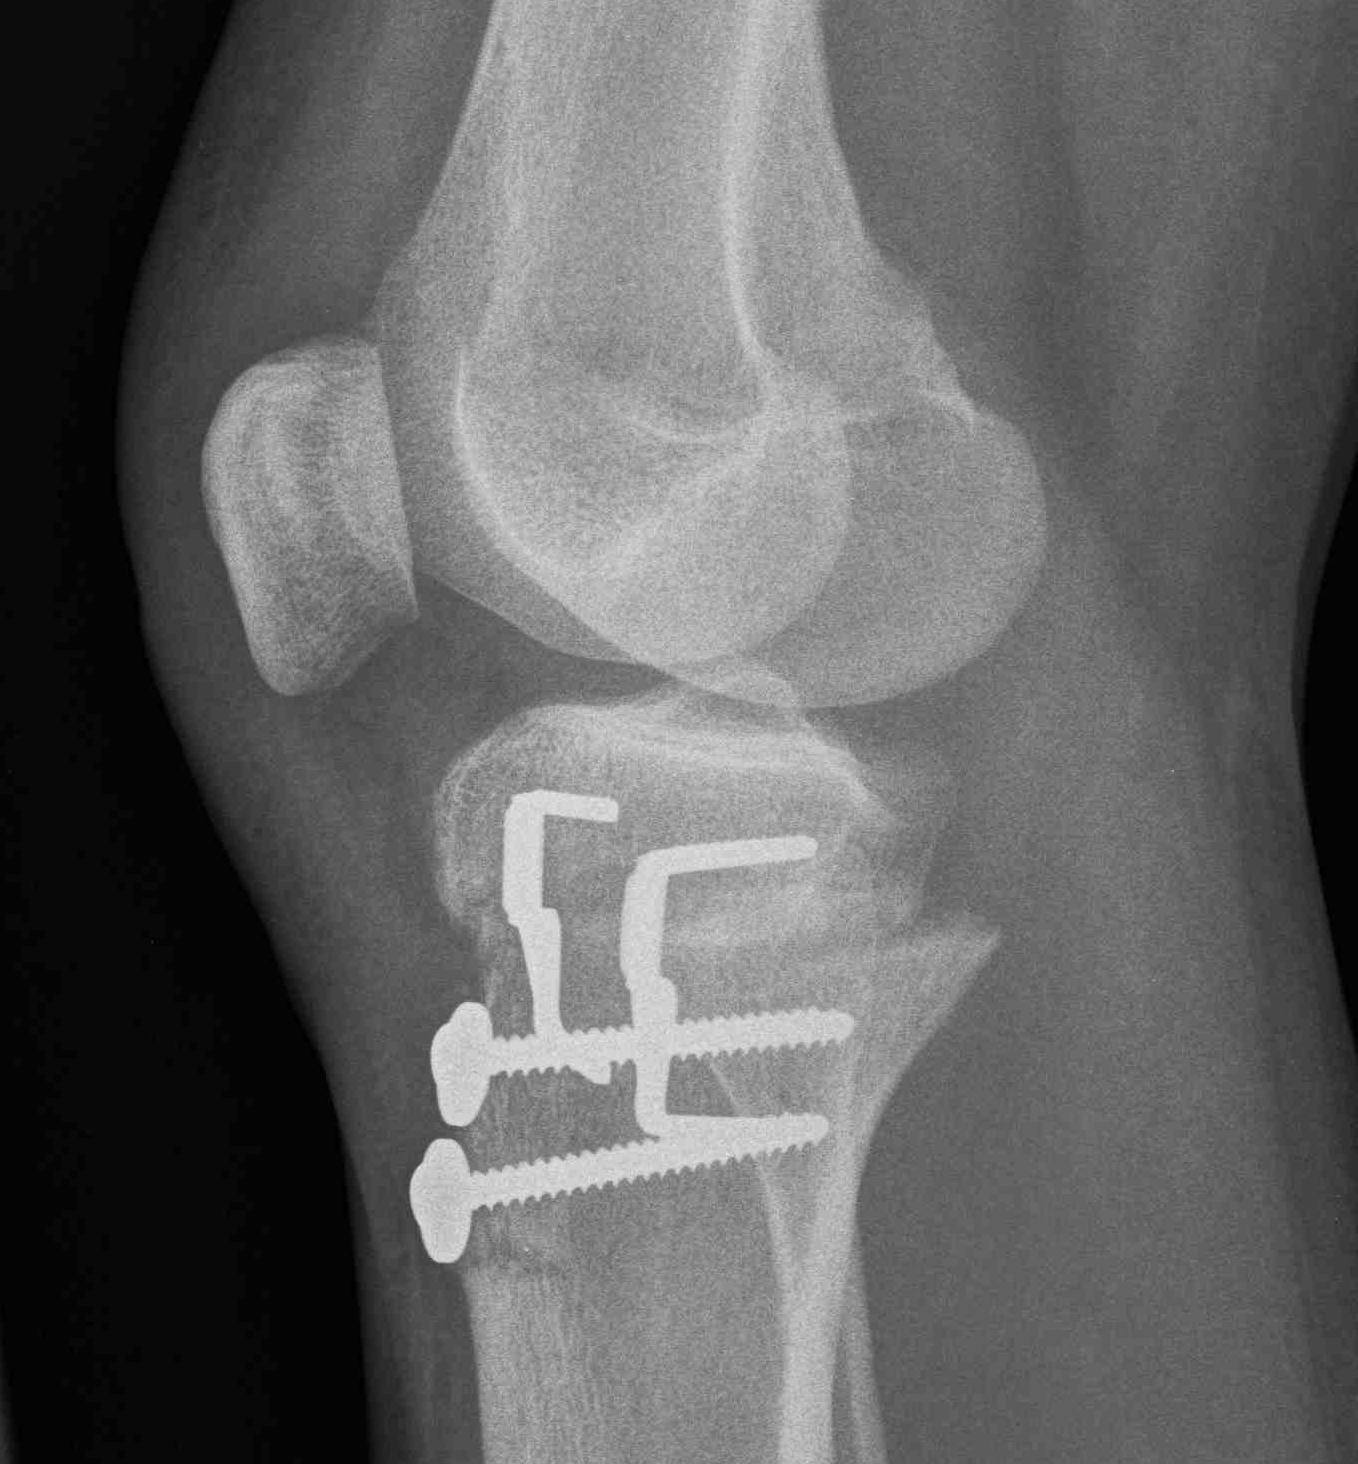

2. Perform TTT (if TTTG > 20)

- incision over TTT

- medialise at least 1 cm

- ensure some element of Fulkerson / anteriorise

- can distalise if patella alta

- secure with screws (2 x small fragment usually sufficient)

- reassess stability

3. MPFL reconstruction (with TTT, or if TTTG < 20)

- acts as checkrein to lateral displacement